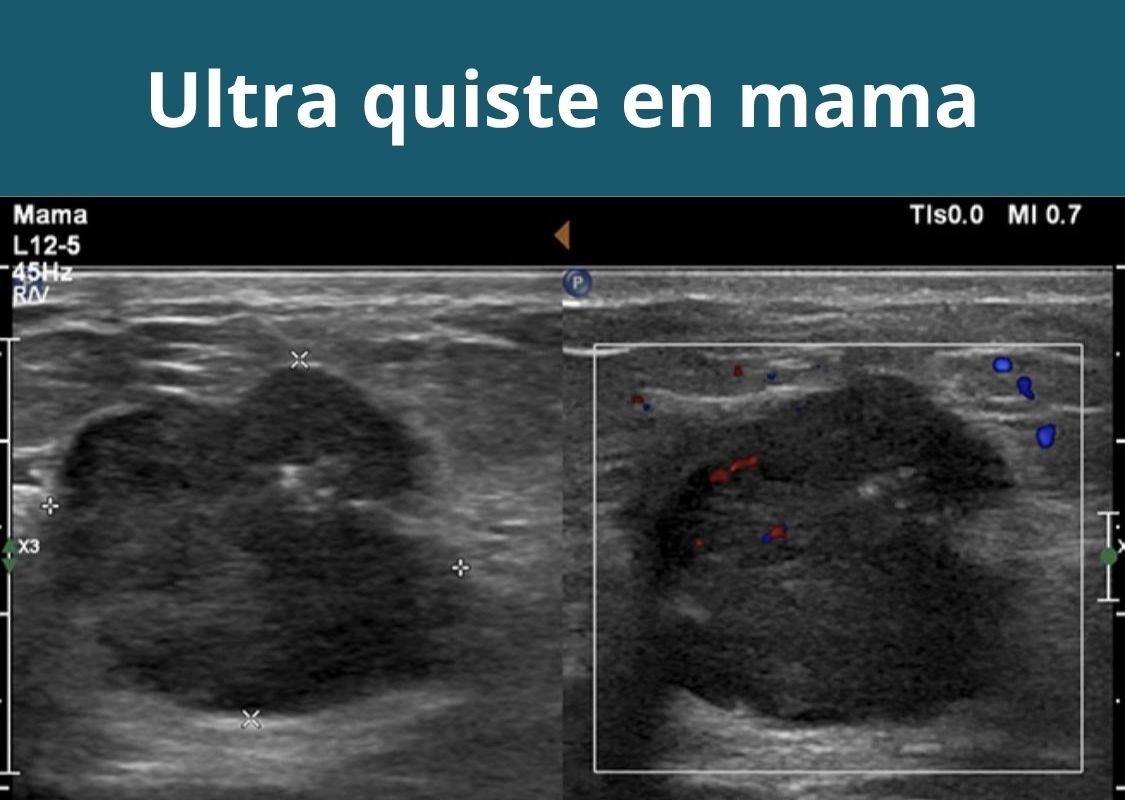

- Ultrasonografía de mamas.

- Para ultrasonido de mamas: no usar desodorante en barra ni productos que dejen residuos.

Otras ultrasonografías